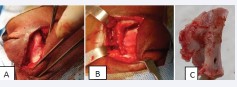

Figure 4: Images (A, B, C) showing a right lateral osteotomy.

Figure 5: Image showing monobloc tumor resection.